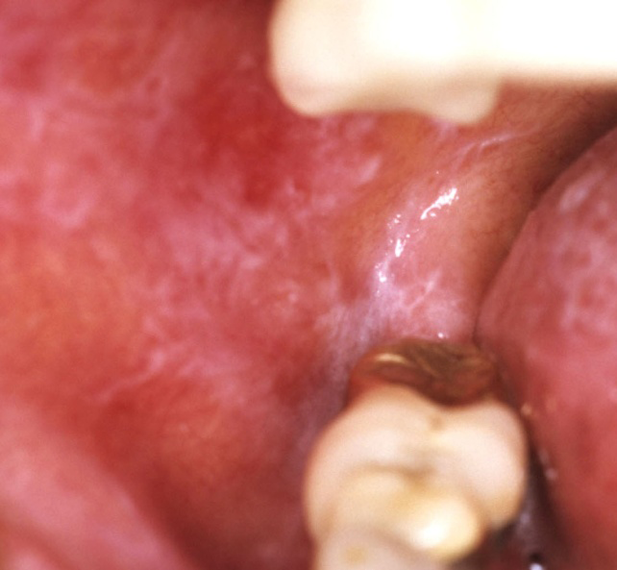

左側頬粘膜扁平苔癬

金属冠と相対する左側頬粘膜に発現した隆起状の扁平苔癬